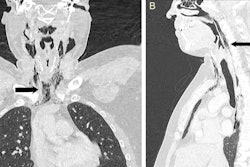

While a urine drug screen and noncontrast head and neck CT scan yielded unremarkable results, CTA (figure A) showed an unexpected multifocal luminal narrowing in the left supraclinoid internal carotid artery, the M1 segment of bilateral middle cerebral arteries, and P1 segments of bilateral posterior cerebral arteries consistent with vasospasm, according to the authors.

A: CT angiography showing unexpected luminal narrowing in the left supraclinoid internal carotid artery, M1 segment of bilateral middle cerebral arteries, and P1 segments of bilateral posterior cerebral arteries consistent with vasospasm. B: CT angiography showing resolution of luminal narrowing after five weeks of supportive care. Images courtesy of BMJ Case Reports 2018."A presumptive diagnosis of thunderclap headache secondary to reversible cerebral vasoconstriction syndrome (RCVS) was made based on the clinical presentation of a severe acute headache, exclusion of aneurysmal subarachnoid hemorrhage, and segmental cerebral arterial vasoconstriction on CT angiography," wrote the authors, led by Dr. Satish Kumar Boddhula of Bassett Medical Center.

While this is the first case of this syndrome that has been reported from chili peppers or cayenne, the authors noted that ingestion of cayenne pepper has been associated with coronary vasospasm and acute myocardial infarction. The patient's symptoms improved with supportive care. He had no further thunderclap headaches, and repeat CTA (figure B) performed five weeks later showed that the luminal narrowing consistent with the syndrome had resolved, according to the authors.